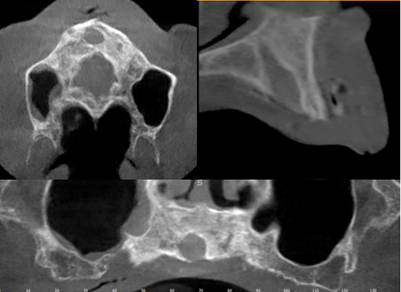

A well-defined unilocular radiolucent image in maxillary anterior region: Nasopalatine duct cyst (Figure 11).

Figure 11: Nasopalatine duct cyst.

Nasopalatine duct cyst (NPDC) is a non-odontogenic, developing epithelial cyst that represents 1% of all maxillary cysts. It is commonly caused by the spontaneous growth of epithelial tissue remains; however, trauma, bacterial infection, and mucus retention can also cause proliferation. Due to its slow growth and asymptomatic character, the cyst is frequently discovered by accident during routine clinical and radiographic tests [7].

Recurrence is rare, occurring in 0-11% of cases, according to reports. Following surgery, full reconstruction of the bones within the bony defect is expected (8). The intra-oral assessment showed diffuse non-tender isolated swelling in the anterior mid-palatal region (Figure 13). Radiographically, it presents as a well-defined oval or round radiolucency in the maxillary anterior tooth region (Figure 14).

Figure 14: Paraxial cut of the cyst.